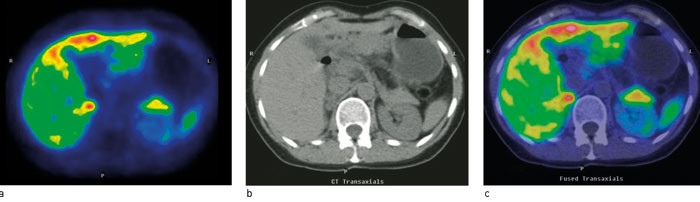

En positronemitterende substans som gir tilsvarende bildeinformasjon som MIBG-scintigrafi, men bedre oppløsning er 11C-hydroksyefedrin (11C-HED) (18, 19). Metoden kan brukes ved mistanke om tumorer fra det sympatiske nervesystemet (feokromocytom, paragangliom, nevroblastom). Det anbefales å seponere en rekke farmaka før undersøkelsen. Opptak er fysiologisk i lever og i alle organer med sympatisk innervasjon (spyttkjertler, hjerte), og stoffet utskilles via nyrene. Fokalt opptak utenfor disse organene er tumorsuspekt, med en sensitivitet på 90 % og en spesifisitet på nesten 100 % (19). Fokalt opptak i en binyre etablerer diagnosen feokromocytom (fig 2). I en studie med 11C-HED-PET hos 12 pasienter med 13 feokromocytomer viste metoden 92 % sensitivitet og 100 % spesifisitet (19).